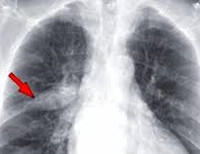

• Рентгенография, КТ грудной полости. Рентген или компьютерная томография пациентов с подозрением на бронхолегочный эндометриоз выполняется повторно для отслеживания динамических изменений. Очаговые тени характерны для данной патологии, инфильтраты определяются за 1-3 дня до менструации и удаляются на 7-10 дней. Кистозные образования сохраняются постоянно, независимо от периода менструального цикла.